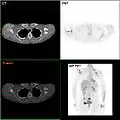

F-18 FDG PET / CT: A انبثاث سرطان الثدي للوح الكتف الأيمن